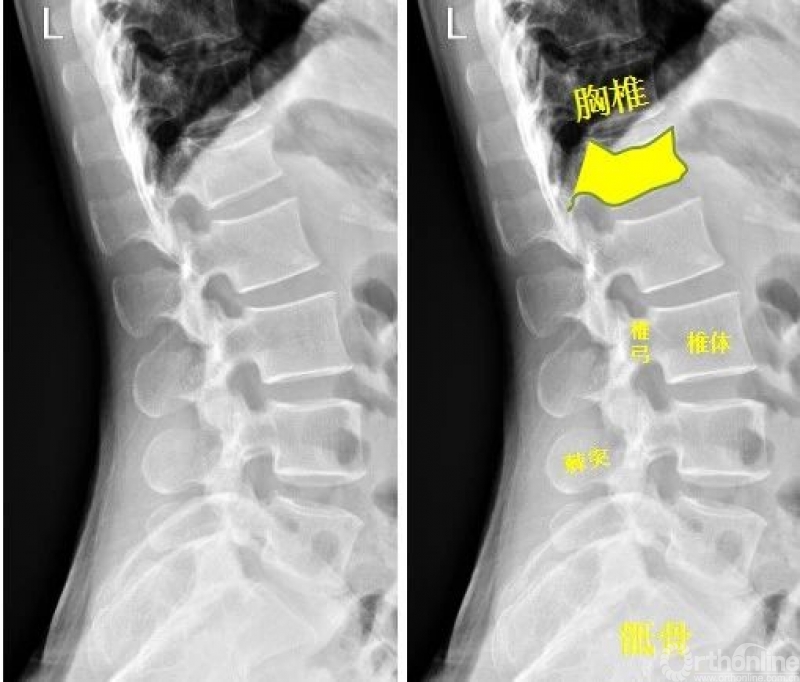

脊柱

腰椎侧位示:第1腰椎呈前低后高楔形改变。腰椎第1椎体陈旧性压缩性骨折

Warmreminder: 陈旧性骨折多在左其他检查时发现,压缩性骨折因受伤时重力向下所致,腰椎、胸椎易发生。

(小妙招此患者腰痛来院,询问病史,十年前从楼上坠落,休息一段时间后无大碍,并没有行检查。)